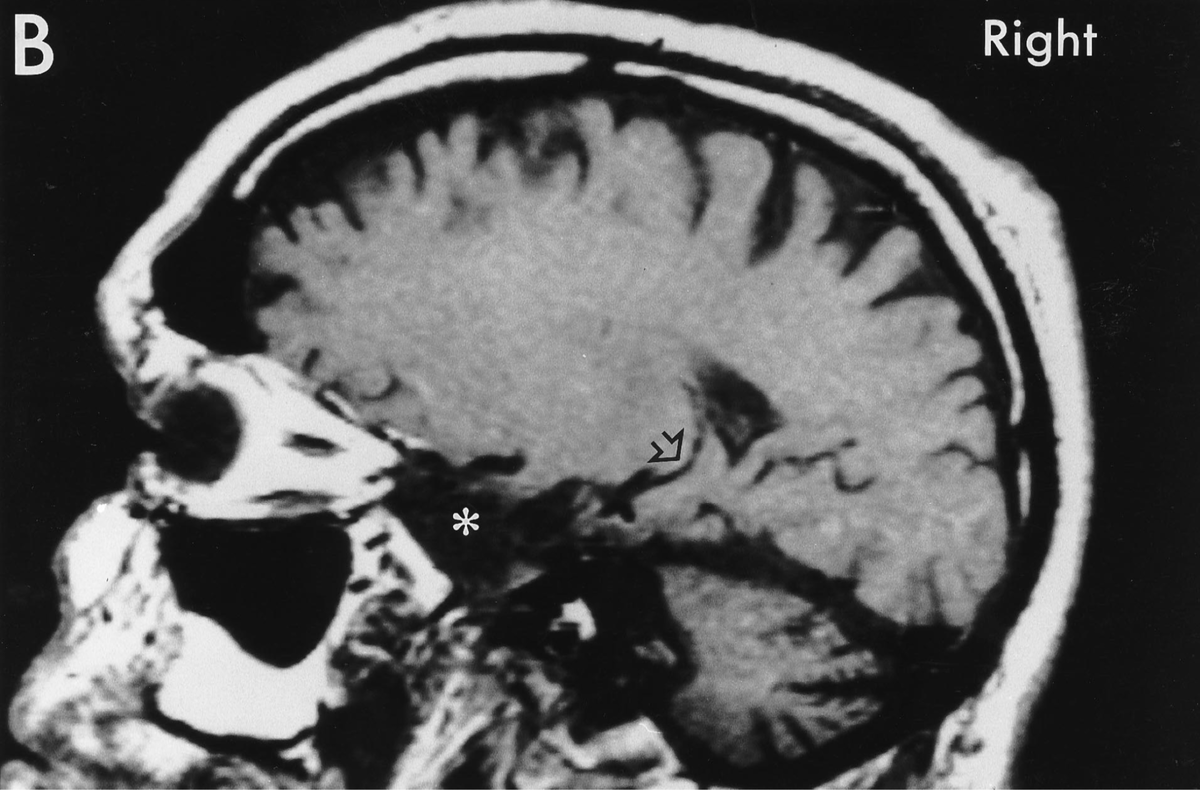

Перед вами — прижизненное МРТ человека, о котором мы уже писали большую статью. При жизни о нем знали только инициалы — H.M., и только после смерти ученые и врачи раскрыли имя уникального пациента, который дал возможность многое понять о человеческой памяти.

К счастью, Генри Молисон сумел прожить после операции еще очень долго: 55 лет. За это время появились томографические методы исследования. Правда, долгое время проводить МРТ боялись: Сковилль «разметил» операционное поле металлическими клипсами, которые так и остались в мозге Молисона. Врачи опасались, что магнитное поле сместит их, что приведет к повреждению артерий и инсульту. Однако позже КТ показало, что все они весьма далеко от сосудов и вот, в 1992 году Молисону прижизненно сделали МРТ на 1,5-тесловом томографе.

Кое-что разглядеть удалось (вы видите показанные поражения стрелкой), однако полную картину ученые так и не получили. Только после смерти мозг Молисона вновь был подвергнут испытаниям: сначала он, в зафиксированном состоянии был изучен на трёх- и семитесловом томографе, что дало исключительное качество картинки (см. фото внизу), а затем исследователь Джакомо Анезе совершил настоящий научный подвиг: 53 часа резал на микротоме замороженный мозг Молисона на 2401 срез толщиной в 70 микрон каждый. Удивительно, что исследователь «запорол» только два образца. И теперь ученые смогли построить полную карту поражений мозга Молисона.